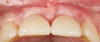

Fig 17. Clinical comparison of the volumetric gain obtained with the intervention, occlusal views. Fig 17: Occlusal view at baseline. Fig 18: Occlusal view at 1-year post-treatment.

Figure 17

Fig 18. Clinical comparison of the volumetric gain obtained with the intervention, occlusal views. Fig 17: Occlusal view at baseline. Fig 18: Occlusal view at 1-year post-treatment.

Figure 18